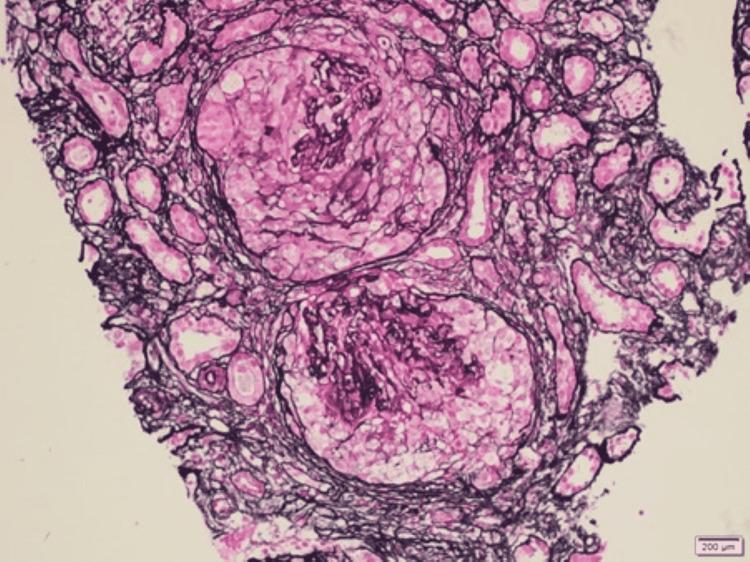

Anti-glomerular basement membrane (anti-GBM) disease is an autoimmune disorder characterized by the production of circulating immunoglobulin G (IgG) antibodies that affect the kidneys and lungs, mainly in the form of rapidly progressive crescentic glomerulonephritis and pulmonary hemorrhage. Typically diagnosed on tissue biopsy, findings mainly include glomerular crescent formation, bright linear staining of GBM for IgG on direct immunofluorescence (IF), and the serologic presence of circulating anti-GBM antibodies. Variation in the laboratory results, where histological findings of linear IgG IF staining were present in the absence of circulating anti-GBM antibodies, have recently led to the use of the term "atypical anti-GBM disease," which usually has a distinct benign clinical outcome as compared to typical anti-GBM disease. We report a case of a middle-aged woman who presented with renal failure without lung involvement. Upon further investigation, the patient was found to have strongly positive serum anti-GBM antibodies, but the tissue biopsy did not show typical findings of the anti-GBM disease. The patient showed modest improvement after multiple sessions of plasmapheresis and steroids, with stabilization of her renal parameters after the initial response. In our case, we will address the possibilities of the discrepancies between the serological and histopathological findings.

抗肾小球基底膜(anti-GBM)病是一种自身免疫性疾病,其特征是产生循环免疫球蛋白G(IgG)抗体,主要以快速进展性新月体性肾小球肾炎和肺出血的形式影响肾脏和肺。通常通过组织活检进行诊断,主要发现包括肾小球新月体形成、直接免疫荧光(IF)下GBM对IgG的明亮线性染色以及循环抗GBM抗体的血清学存在。实验室结果存在差异,即在线性IgG IF染色的组织学发现存在时却没有循环抗GBM抗体,这最近导致了“非典型抗GBM病”这一术语的使用,与典型抗GBM病相比,其通常具有明显不同的良性临床结局。我们报告一例中年女性病例,该患者出现肾衰竭但无肺部受累。进一步检查发现,患者血清抗GBM抗体呈强阳性,但组织活检未显示抗GBM病的典型表现。经过多次血浆置换和类固醇治疗后,患者病情有适度改善,初始反应后肾脏参数稳定。在我们的病例中,我们将探讨血清学和组织病理学结果之间差异的可能性。